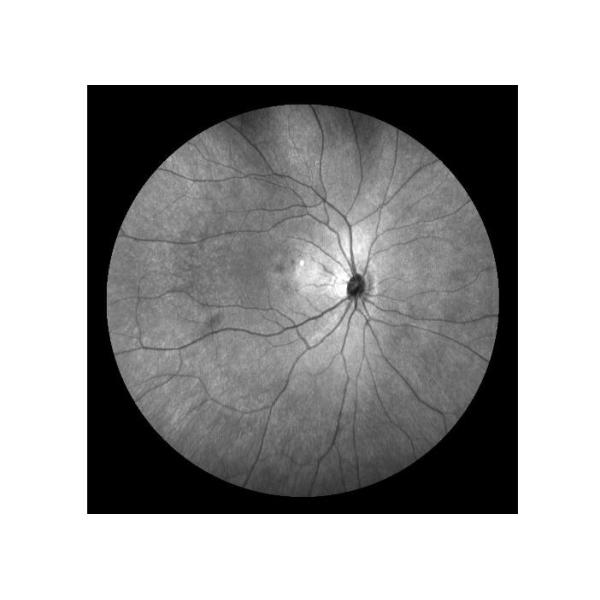

Ultra-wide Field Laser Scanning Retina Angiograph Digital Ophthalmic Equipment With Optical Zoom 100°/60°/30°

China Leading And Domestic Initiative Confocal Laser Scanning Technology, to Realize Fundus Reflex And Capillary

fluorescence Imaging.

Cases

Retina Angiograph Digital 160° Ophthalmic Equipment Images |